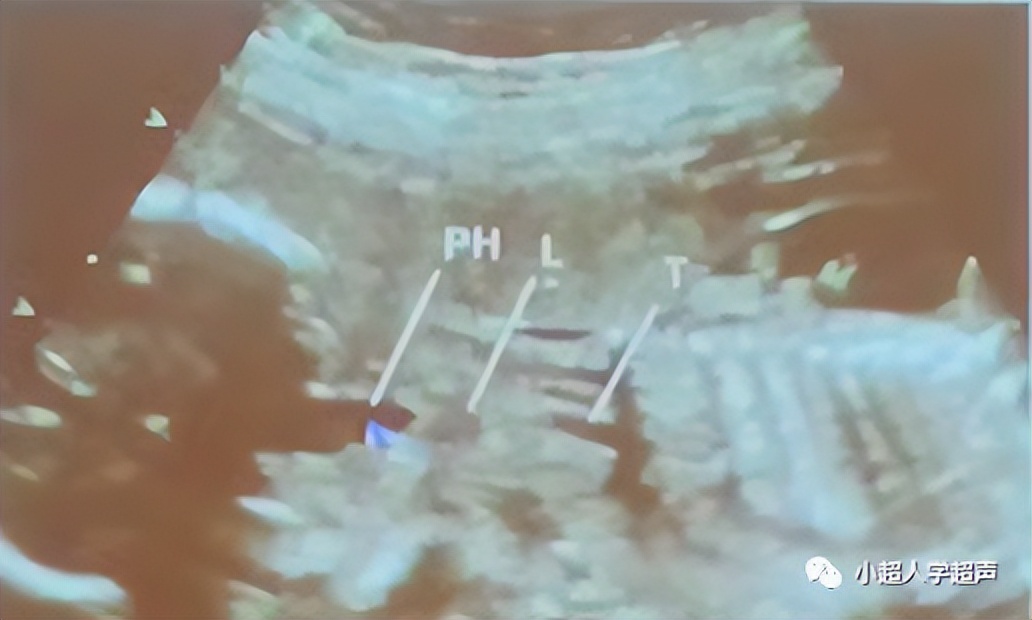

超声表现为四条线状高回声,代表食道的前后壁。食道内因胎儿吞咽偶尔可见液体,因而可显示为一根细小的管道。

由于食道并不成一条直线,多数情况下显示整体结构比较困难。颈部、胸部和腹部部分可分别显示。

- 颈段食道在矢状面显示最佳

- 胸段则在气管后面,与气管平行

- 最远端的腹部部分偏离脊柱,在胃的入口处可以看见。